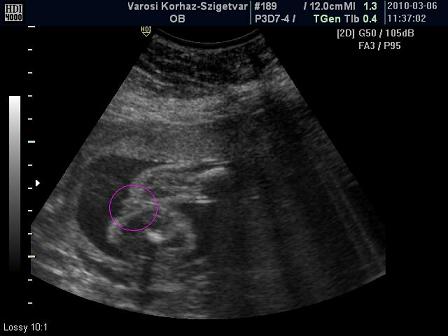

Csipet! Naaaaagy gratul a kis kukacoshoz

Maki nektek meg a tuti kiscsajhoz

De jók a képek!!

Zsani! Jajj de jó, hogy megnyugtattak

Freyja, szerintem az AFP eredmény miatt ne aggódj!

És ez aszakemberek véleménye is

A lényeg az UH, meg az eddigi eredmények!!